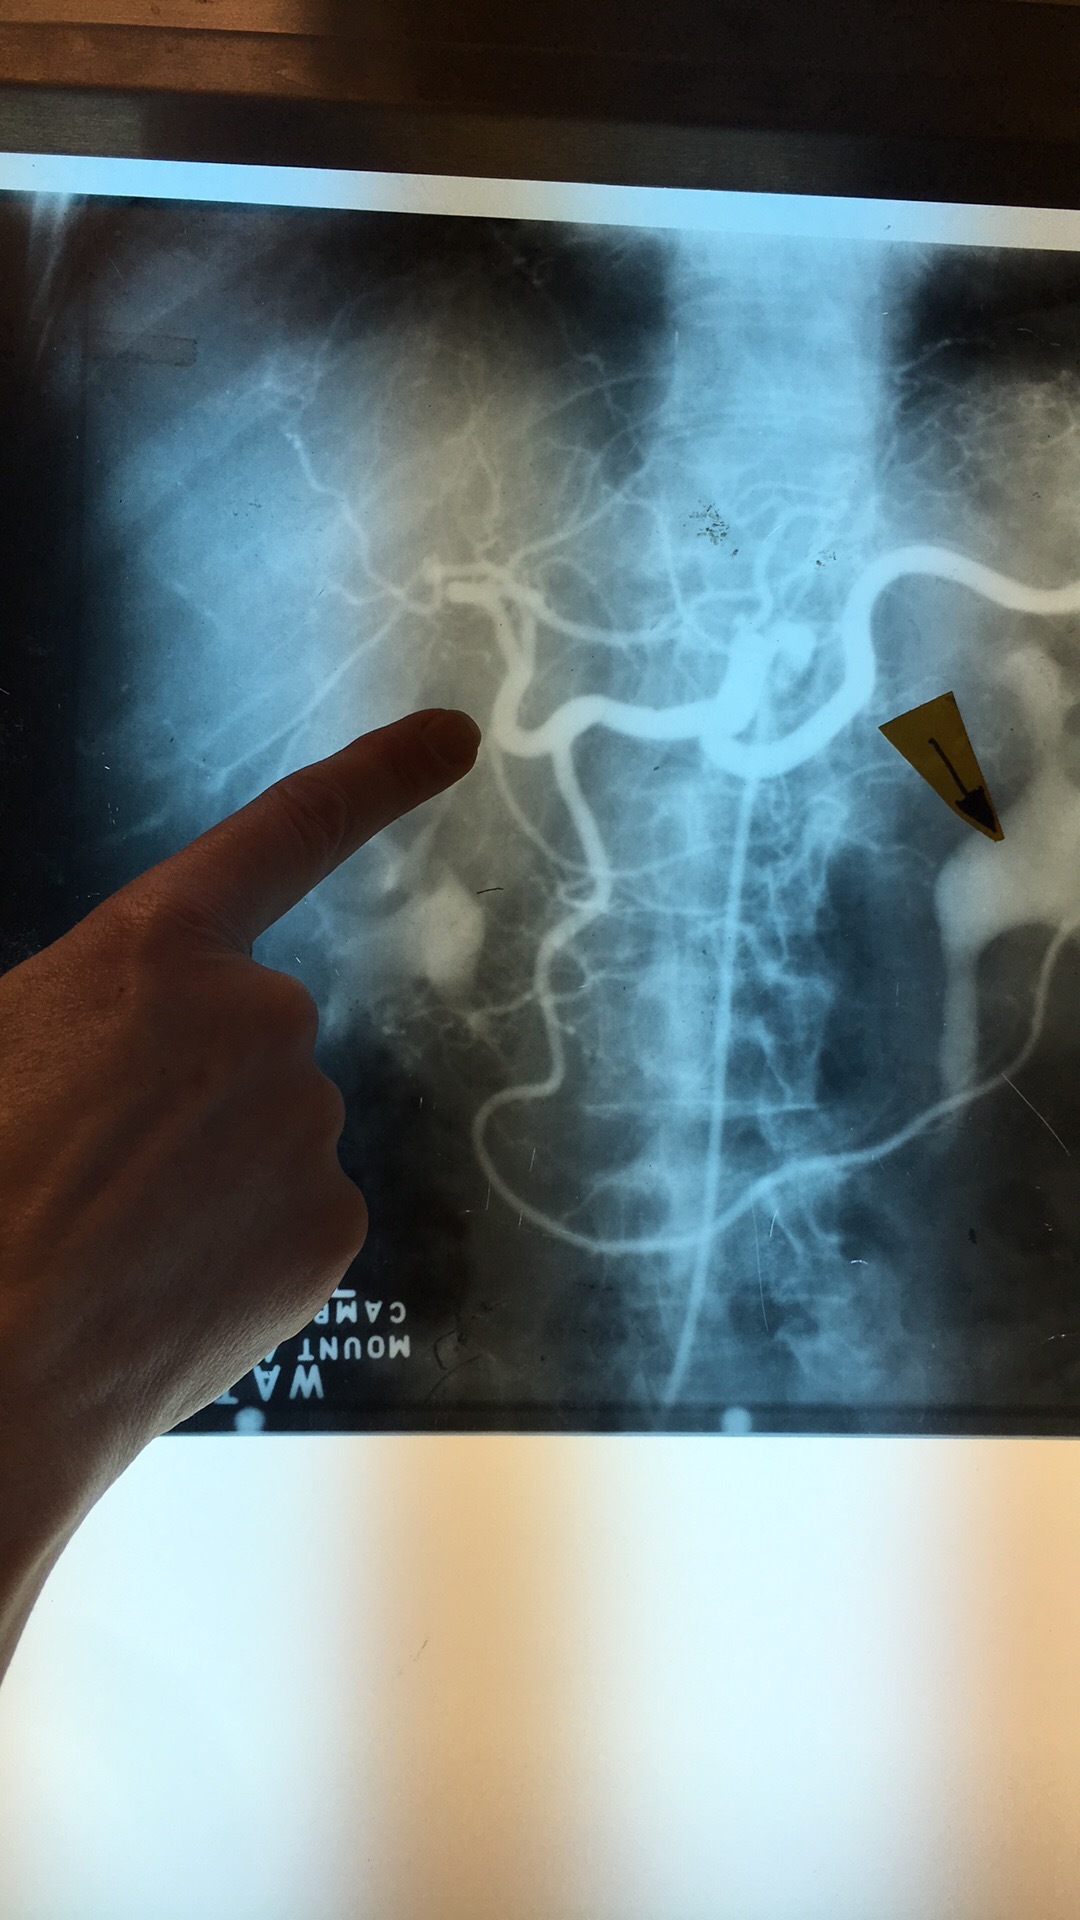

Which artery?

Inf Mesenteric Art